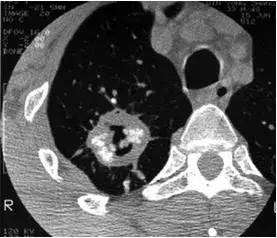

CT征象—附:晕轮征

晕轮征(halo sign):是指结节周围环绕的类环形的磨玻璃样密度影。通常代表肺出血与水肿。一般是侵袭性真菌病的早期征象;也可见于炎症、肿瘤与结核病等疾病中。

霉菌球周围晕征

肺泡癌周围晕征

侵袭性肺曲霉菌病